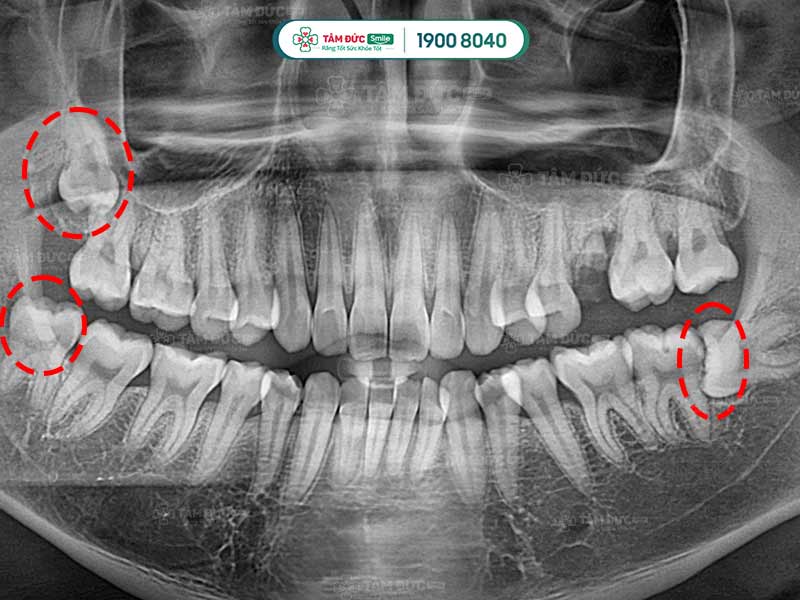

Quý khách có thể nhận biết răng khôn mọc ngầm thông qua phim chụp X-Quang

- Răng khôn mọc ngầm bị lệch, ảnh hưởng đến răng lân cận (răng số 7).

- Răng khôn mọc ngầm ác tính: xuất hiện các u nang gây ảnh hưởng xấu đến cấu trúc xương hàm.

Trước khi nhổ bỏ răng khôn mọc ngầm, Quý khách được bác sĩ chụp X-quang răng và thực hiện các xét nghiệm máu cần thiết. Qua phim X-Quang, bác sĩ biết được ảnh hưởng của răng đang mọc ngầm để cân nhắc phương pháp điều trị thích hợp nhất.